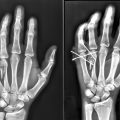

34 Fixation of Uni and Bicondylar Phalangeal Fractures

Evaluation must take into account (1) angulation or malrotation at the fracture site; (2) fracture pattern to judge stability; (3) and status of the surrounding soft tissues. Operative management is focused on restoring articular congruity and fracture stability. The priorities in postoperative management for isolated condyle fractures are early range-of-motion and edema management, given the propensity for PIP joint stiffness.

No intra-articular displacement should be tolerated as this will likely lead to angulation of the digit. 5

If managed nonoperatively, nondisplaced oblique fractures should be followed closely with weekly X-rays for a minimum of 3 weeks.